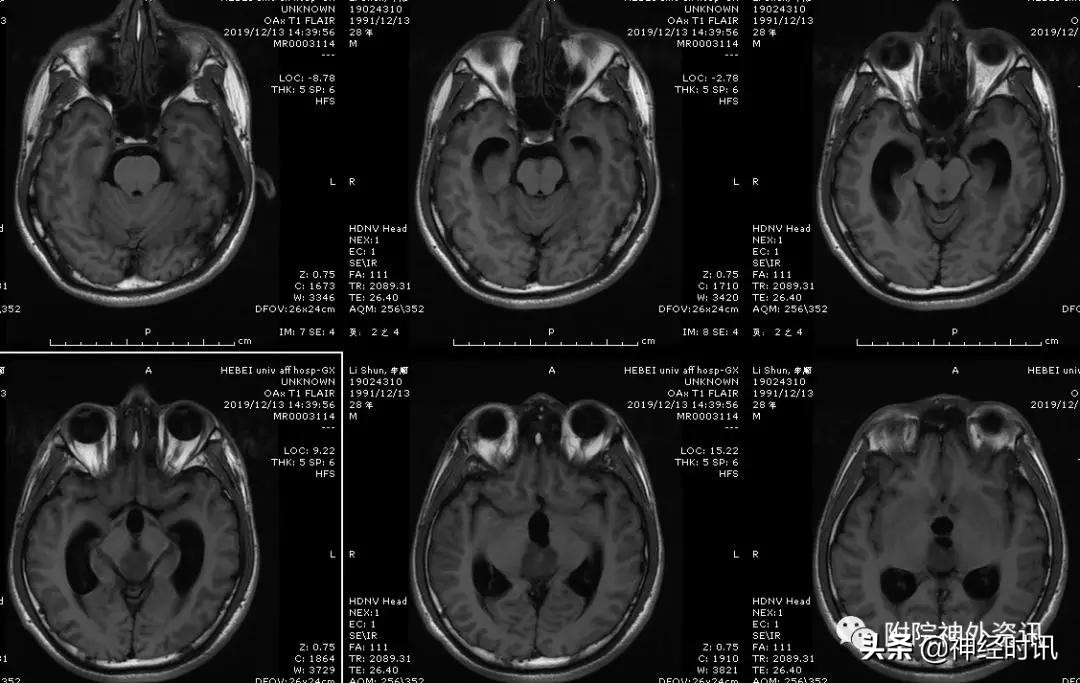

男性,28岁,主因复视20余天入院,查体双瞳孔不等大,直径左=3. 5mm,右=3.0 mm,对光反射迟钝,双眼上视困难,左眼眼位异常,向内下斜视。